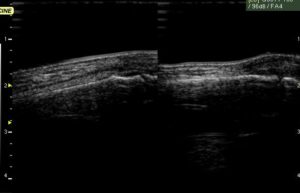

小指の超音波画像で、左が患側、右が健側です。

骨折を疑わせる異常画像が見られます。

整形外科の先生にレントゲン検査をしていただきましたが、

レントゲン上の骨折は見られませんでした。

超音波観察を行っていると時々このような事が起こります。

このようなケースは治療期間が長くなるので注意が必要です。

骨に相当負担がかかったことがうかがえます。